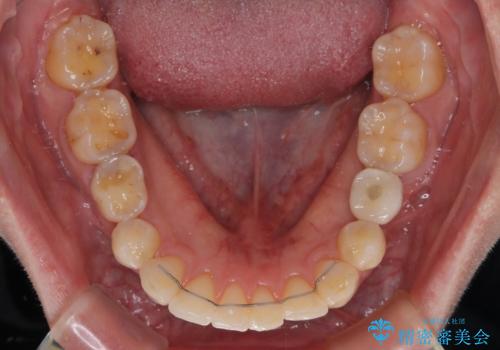

- 全体的なデコボコと左下乳歯部の欠損を気にして来院された患者様です。

乳歯が抜け落ちた後の後続永久歯が欠損しているため、スペースが残っておりました。

口元の突出感を気にしているのであれば欠損スペースを利用して抜歯矯正を行うことも可能ですが、横顔の印象はスッキリとしている状態であったため、矯正治療でスペースを閉じきることは不可能と判断し、インプラントによる補綴治療を行うこととしました。

第二小臼歯の欠損によるが乳歯残存や欠損が多く、この乳歯は後続永久歯に比べて幅が非常に大きいため、教聖地料によるスペースクローズが難しいことが一般的です。